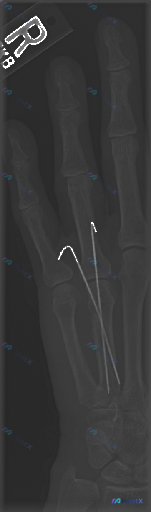

右手克氏针内固定术后X光:最该警惕的「偏离正常」不是骨折线

整理一份右手指部的X光正位影像资料,最醒目的是两枚金属克氏针——一枚从第3掌骨基底部穿到近节指骨,另一枚对应第4指,两根都跨了掌指关节,近端还在皮下留了钩状弯曲。

骨皮质能看到不连续或者陈旧性骨折线的痕迹,目前没看到明显的溶骨、广泛骨膜反应,植入物周围也没有透亮带。